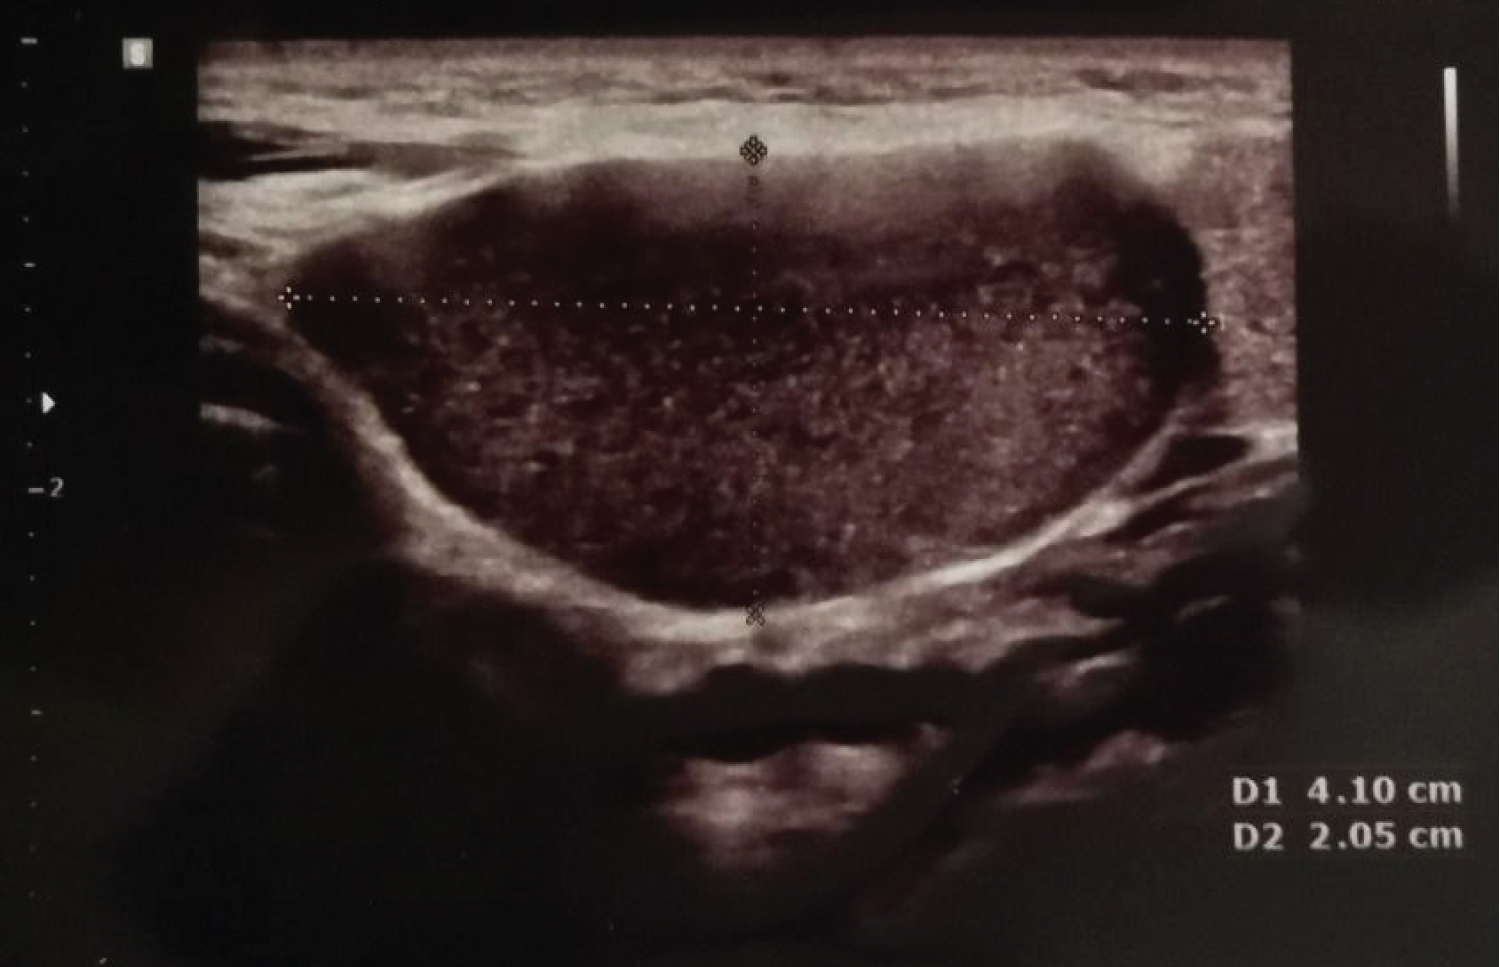

We report on a healthy 30-year-old pregnant woman who presented a right sided tense-elastic neck swelling, starting from the seventh month of pregnancy (Figure 1). The ultrasound examination demonstrated a 41 × 20 mm oval cystic formation characterized by corpuscular content, localized at right mandibular angle in a space between the submandibular and parotid gland. The formation shows no vascular enhancement at Doppler sampling, being compatible with a branchial cleft cyst arisen from the second cleft. Nearby structures were deemed normal, no lymphadenopathy was detected (Figure 2). An iterative clinical and ultrasound check demonstrated its progressive growth, reaching maximum expansion at delivery. The cyst did not cause any pain or functional impairment. MRI examination of the neck, conducted after delivery, confirmed the known cyst, 38 × 40 × 48 mm in size with an oval morphology and clear limits, without infiltrating characteristics, with a finely structured proteinaceous sedimentation, located at right lateral neck compartment, antero-medial to the sternocleidomastoid muscle. No significant loco-regional adenopathies were documented, the adipose layers were preserved, and the parotid and submandibular glands were free from focal alterations. These findings were compatible with Bailey type II second branchial cleft cysts [4,5,9,10] (Figure 3). After delivery, the cyst remained stable for about four months and then gradually shrunk within a month. Subsequently surgical excision was performed. The surgical material was sent for histological examination, which confirmed the diagnosis of second branchial cleft cyst and detected the positivity at immunohistochemistry for ER on the lining epithelium using anti-ERα (SP1) antibodies (Figure 4).

Figure 2: Transverse section of a second branchial cleft cyst ultrasound scan showing an anechoic content with a few hyperechoic spots and no vascular enhancement. View Figure 2